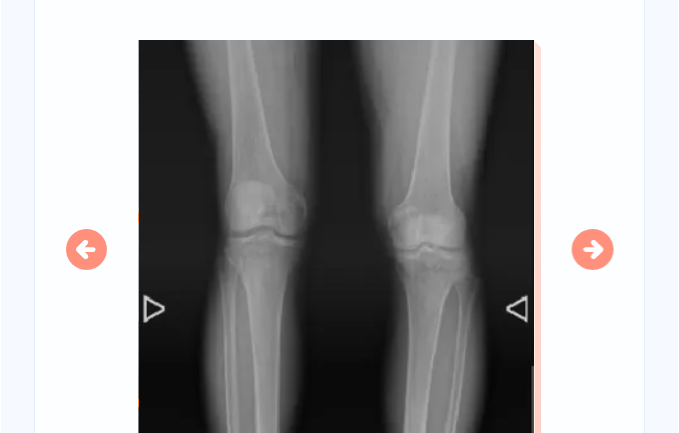

无意中,去年12月,郭大叔在电视上看到北京积水潭医院郑州医院揭牌,骨科专家还要来郑州坐诊。治了几十年的病,郭大叔很清楚北京积水潭医院的实力,立刻拨打郑州大学附属郑州中心医院96595预约。北京积水潭医院郑州医院副院长杨德金认真查看了郭大叔的影像资料,检查了髋关节功能,发现其下肢短缩3cm,右髋关节基本没有活动功能。

图中可明显看到患者右侧髋臼骨质增生严重

杨德金详细向郭大叔及家人讲述了目前国内外的相关治疗方案,并给出专业的治疗建议——右侧人工全髋关节置换。正是这次高效的沟通,原本执拗的郭大叔思想开始动摇,和家人商量后,决定预约手术治疗!